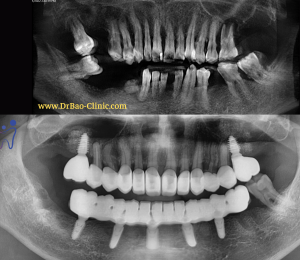

After check up clinician and X-ray:

After check up clinician and X-ray:

– All his teeth were prepared for crowns.

– Gum got inflamation and bleeding a lot whenever he brushed his teeth.

– Teeth were sensitive with water, even normal water.

– Periodontal disease treatmetn.

– Remove all his old crowns.

– Remove the hopeless teeth.

– Design full mouth rehalibitation and restore by implants and zirconia crowns.